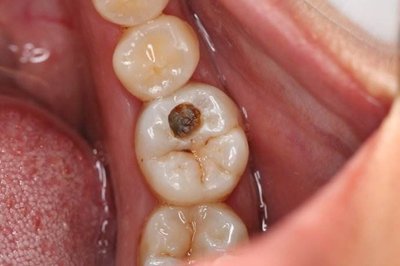

龋齿龋坏的程度怎么分 龋病的形成首先是牙釉质磷灰石晶体的破坏,使得透明而有光泽的釉质变混浊呈现出白垩色斑病变范围逐渐扩大并向深层发展,使牙本质脱钙变软。食物与细菌代谢产生的色素连同牙... 牙齿治疗 朱小溪 1138 2024-03-23

龋病按病变程度怎么分类 龋病是发生在牙体硬组织上慢性、进行性破坏的细菌性疾病。临床表现为牙体硬组织色、形、质各方面发生变化,随着硬组织脱矿和有机物分解的进行,最终牙体组织崩解形成不可自... 牙齿治疗 范姜英杰 914 2024-03-11

龋齿的分类有哪些 按病变深度分类根据病变深度可分为浅龋、中龋和深龋。这一分类方法在临床上最为适用。牙骨质龋多表现为潜掘性龋或表层剥脱,由于牙骨质较薄,尤其是牙颈部,因此病变可很快... 牙齿治疗 吴芳芳 726 2023-11-27